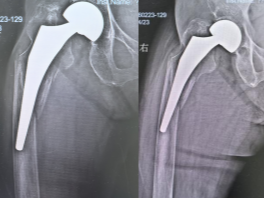

患者术前 X 线片 患者术后X线片

该患者在14年前因股骨颈骨折,在我院接受了人工股骨头置换术,此次因外伤导致假体周围Ⅳ型骨折再次入院。患者属于超高龄人群,加之此类骨折在临床上较为罕见,手术难度及围手术期风险极为突出。骨科医院副院长李宏伟带领团队高度重视,迅速完成各项术前检查与准备,并联合医务部,组织呼吸与危重症医学科、重症医学科、心血管内科、麻醉手术科等多学科专家进行会诊。经深入讨论,专家团队为患者制定了周密、个性化的手术方案。